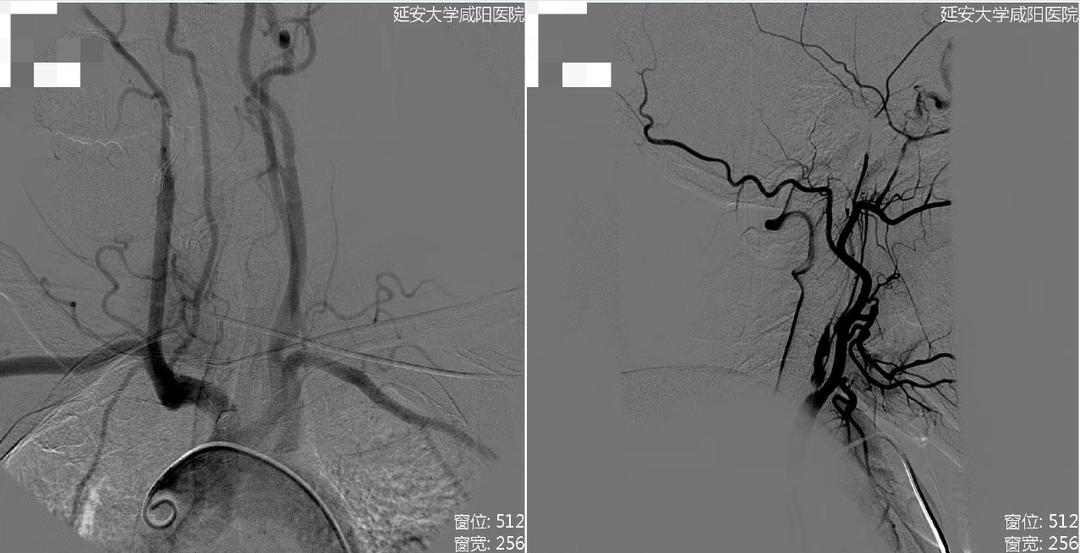

右侧颈总动脉造影

病历夹什么径技·第152期|串联营病历夹:川陕大营_https://www.jmylbn.com_新闻资讯_第46张

病历夹什么径技·第152期|串联营病历夹:川陕大营_https://www.jmylbn.com_新闻资讯_第47张

<<滑动查看下一张图片>>

• 出院时,患者意识清楚,精神可,夜休可,食纳可,大小便正常。

• 查体:生命体征平稳,心肺腹查体大致正常。神经系统查体基本同术前。(NIHSS评分1分)